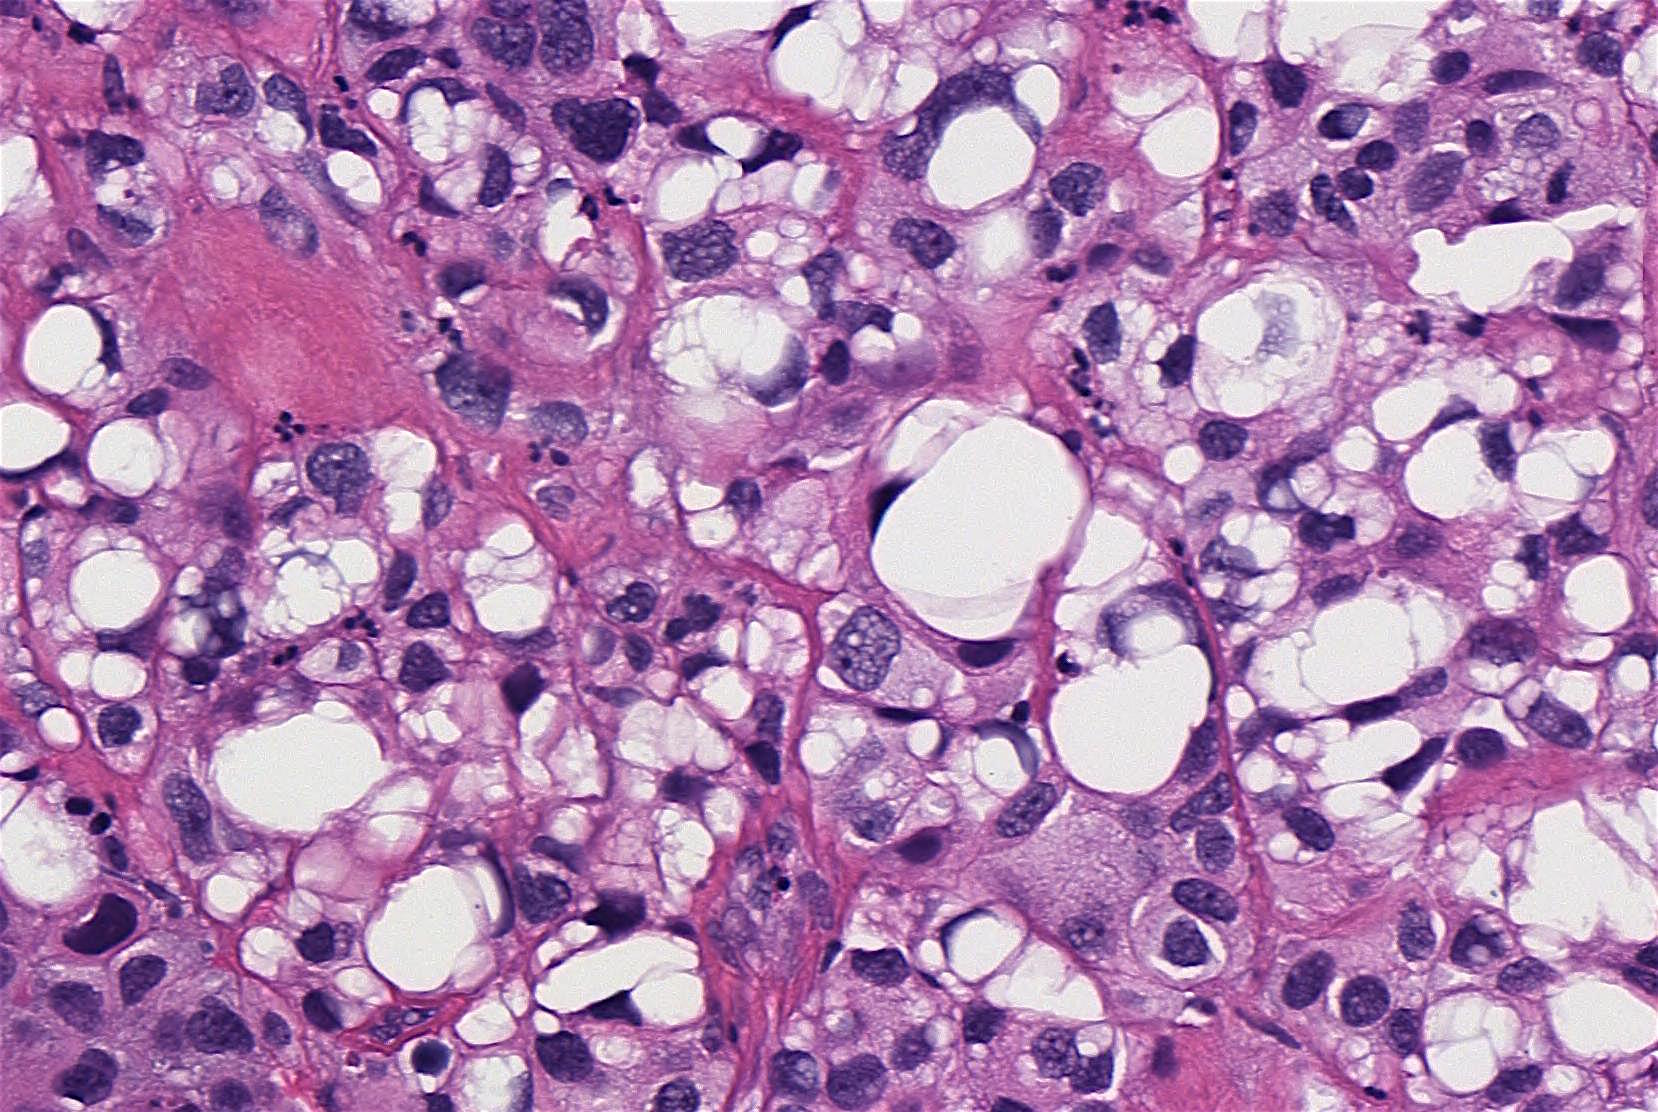

Pathology Outlines Lipidrich Spindle Cells Urothelial Carcinoma Invasive urothelial carcinoma cystoscopically and grossly may present as a polypoid, sessile, fungating ulcerated and/or. Spindle cell lesions in the bladder can be challenging and present a wide differential diagnosis. Sarcomatoid urothelial carcinoma (uca) is a rare but aggressive variant of bladder cancer that can show diagnostic challenges even. Sarcomatoid urothelial carcinoma (suc) is a rare and highly malignant form. Spindle Cells Urothelial Carcinoma.